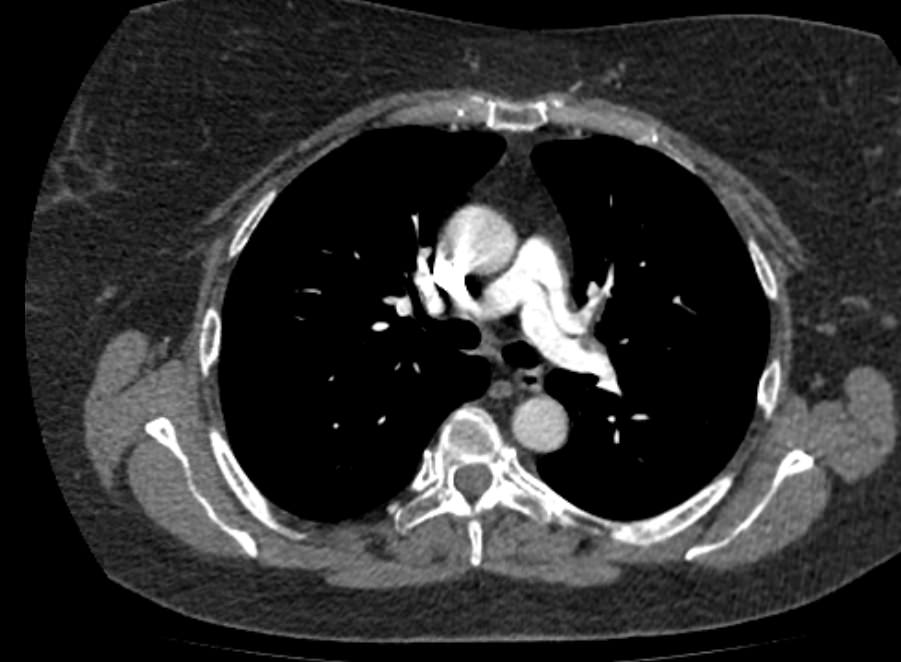

Легочный ствол отходит от правого желудочка сердца, затем разветвляется на правую и левую легочные артерии, которые несут венозную кровь от всего тела к легким для насыщения ее кислородом. Легочные артерии разветвляются на сосуды меньшего калибра, самые мелкие из которых – легочные капилляры – образуют густую сосудистую сеть, где непосредственно происходит обогащение крови кислородом.

Патология легочной артерии может проявляться повышением давления внутри просвета сосудов. Это состояние называется легочной гипертензией и развивается на фоне заболеваний сердечно-сосудистой системы, обструктивных заболеваний легких. Кроме того, легочная гипертензия сопутствует порокам развития дыхательной системы, клапанов сердца, а также может быть следствием многих других болезней, например, гемолитической анемии и системных заболеваний соединительной ткани.

Еще к частым патологиям легочной артерии относится стеноз (сужение просвета) легочной артерии, который может быть врожденным и приобретенным, и тромбоэмболия легочной артерии (ТЭЛА).

Наиболее информативным, при этом быстрым и неинвазивным (то есть без вмешательства в организм пациента), методом диагностики патологии легочной артерии является мультиспиральная компьютерная томография (КТ-ангиография). Методика основана на использовании рентгеновского излучения в сочетании с цифровой обработкой данных для получения трехмерных изображений сосудистой системы.

Для визуализации кровеносных сосудов в обязательном порядке применяется контрастное усиление. Для этого в вену пациента вводится йодсодержащий контрастный препарат, который попадая в кровоток активно поглощает рентгеновские лучи и ярко контрастирует сосудистую систему, в том числе легочной артерии, на фоне окружающих тканей. Использование контраста дает возможность визуализировать даже мелкие артерии и выявить патологию.

В наших диагностических центрах КТ-ангиография легочной артерии проводится на современных мультиспиральных компьютерных томографах экспертного уровня TOSHIBA AQUILION. Оснащение аппаратов позволяет получать детальные снимки и трехмерные изображения сосудистой системы легочной артерии, при этом применение скоростной мультисрезовой методики сканирования значительно снижает уровень лучевой нагрузки на пациента.